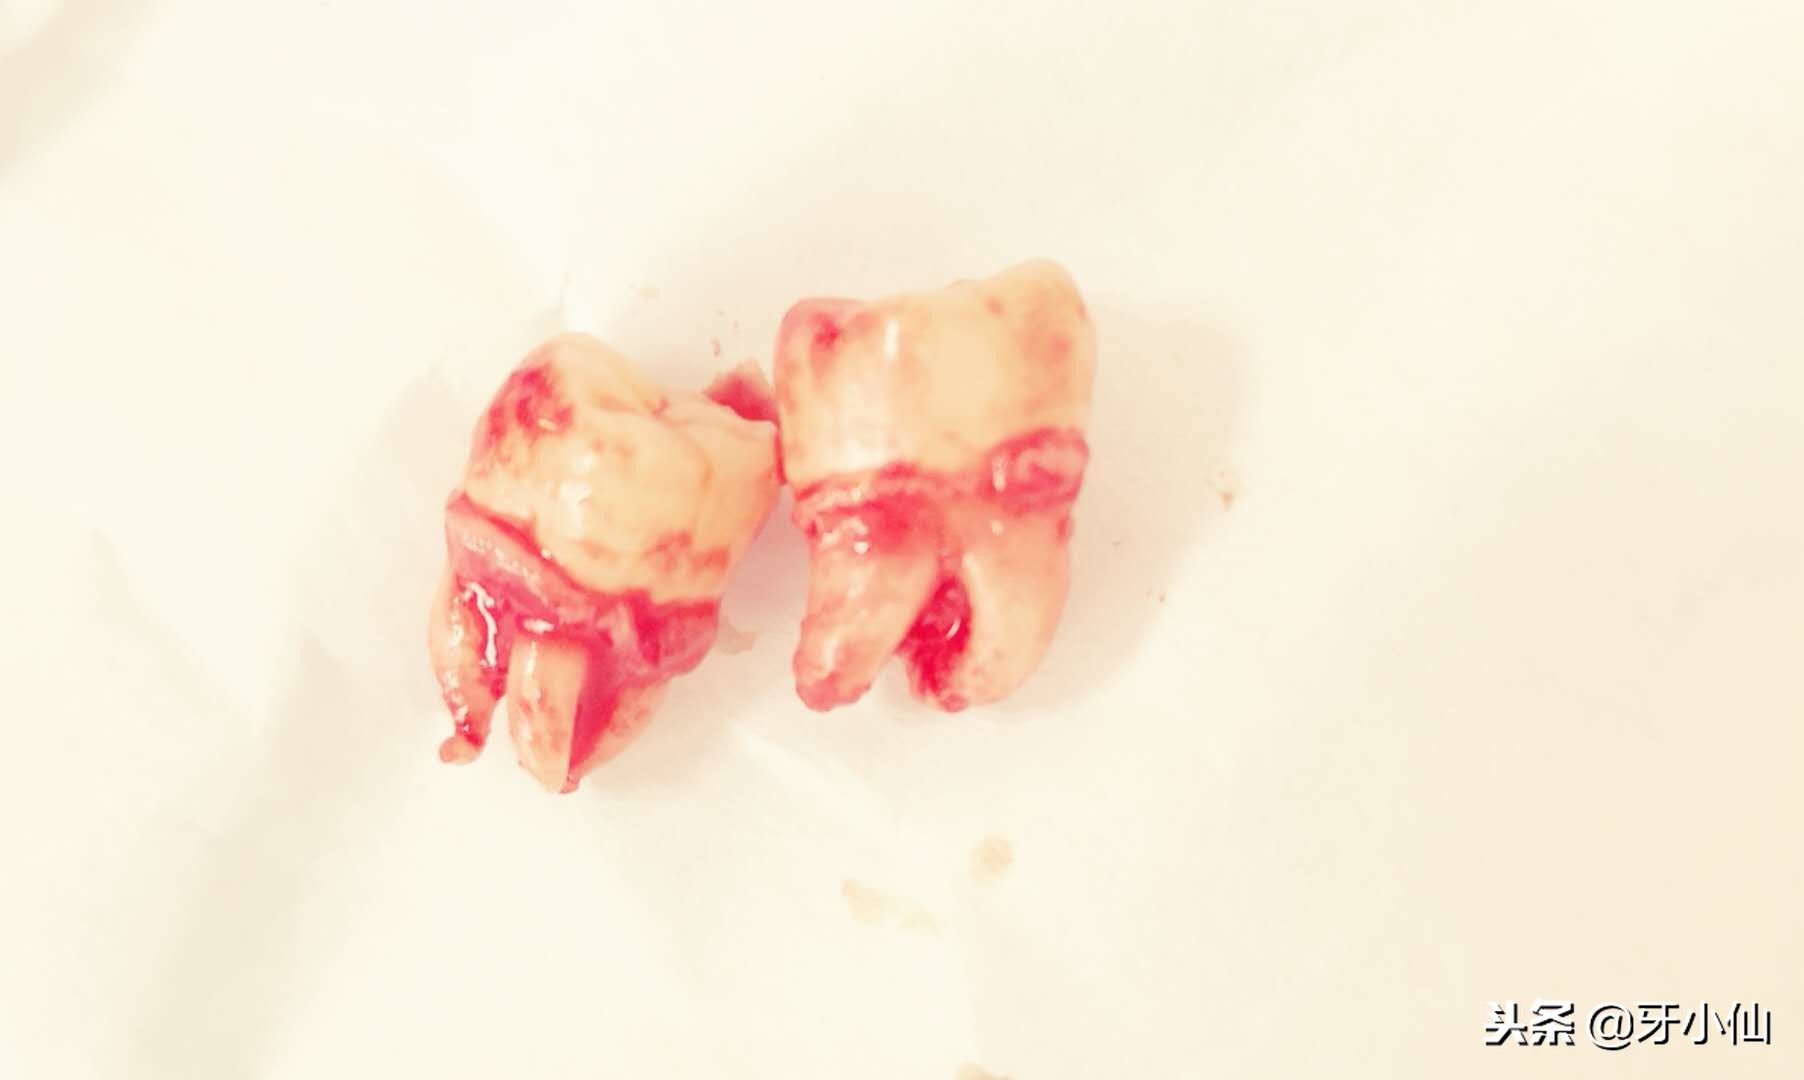

拔出来的智齿~